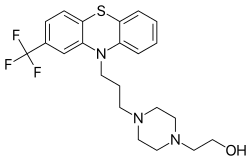

IUPAC name

| Formula | C22H26F3N3OS |

| Molar mass | 437.53 g·mol−1 |

SMILES

InChI

Fluphenazine is a typical antipsychotic of the phenothiazine class.[1] Its mechanism of action is not entirely clear but believed to be related to its ability to block dopamine receptors.[1] In up to 40% of those on long term phenothiazines, liver function tests become mildly abnormal.[5]